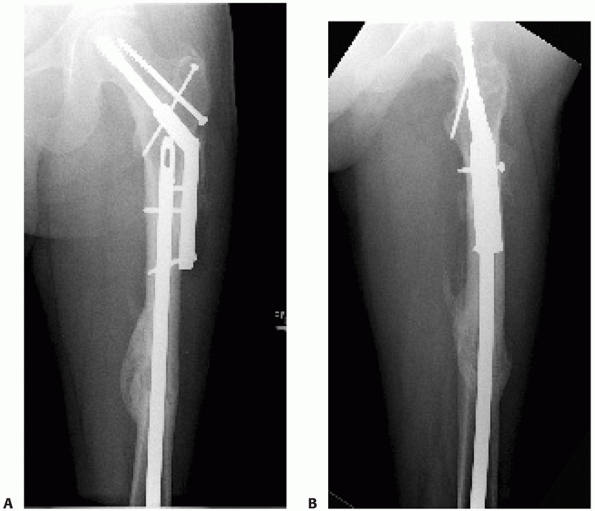

![]() |

FIGURE 50-10 Femoral plating for a simple fracture pattern. Plate length and screw position are more important than screw number.

FIGURE 50-11 This 74-year-old male sustained a periprosthetic femoral shaft fracture after a motor vehicle crash (A, B). He had no previous problems with his hip prosthesis. The femur was plated using an extensile lateral approach (C-F).

Given the spiral fracture configuration, a direct fracture reduction with lag screw fixation was performed. A long neutralization plate that spanned the entire femur was used. |